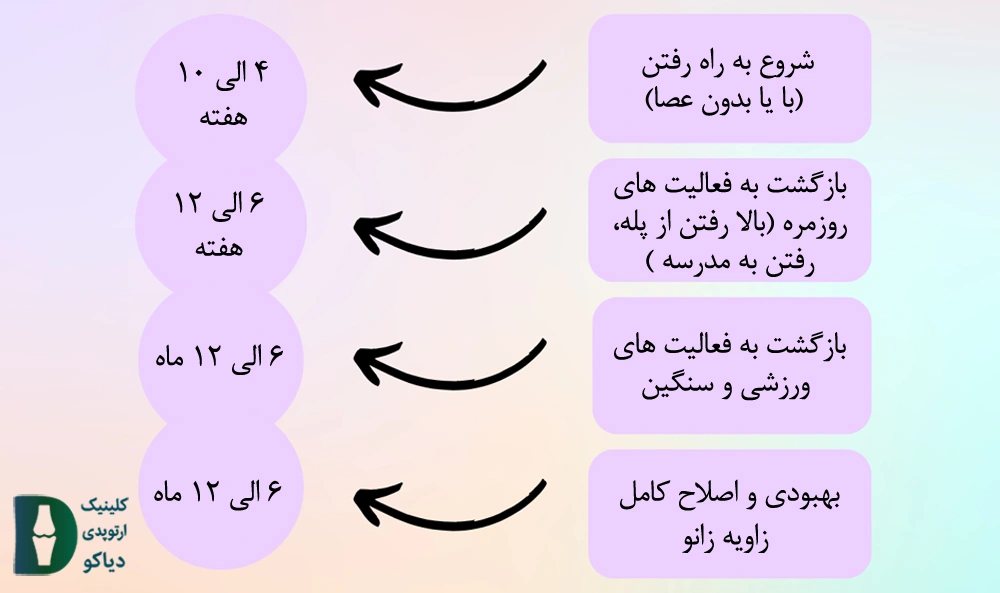

اگر چه زمان دقیق بازگشت به فعالیت به عواملی نظیر ویژگیهای بدنی فرد و … بستگی دارد. اما با این حال در شکل زیر زمان بازگشت به فعالیت در مراحل مختلف بهبودی به نمایش درآمده است: